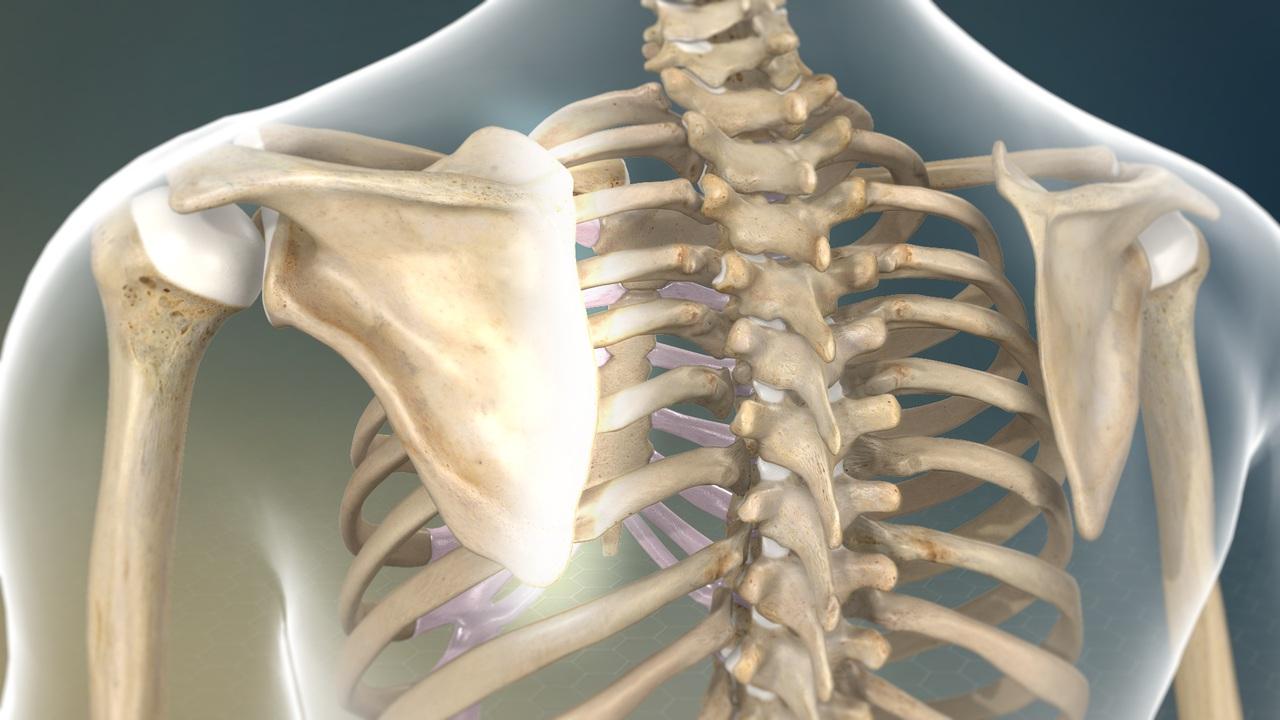

肩胛骨是一塊位於背部、形狀如三角形的扁平骨,靠肌肉固定在肋骨上,能進行上舉、下壓、內收、外展、前傾與後傾等6個方向的運動。專業體育選手身心教練桑塔斯(Dana Santas)表示,這種靈活性讓我們能完成許多動作,如投球、舉重或推拉,但也意味著,若肌肉力量不平衡,肩膀就容易失去穩定支撐。

肩胛骨是一塊位於背部、形狀如三角形的扁平骨,靠肌肉固定在肋骨上,能進行上舉、下壓、內收、外展、前傾與後傾等6個方向的運動。